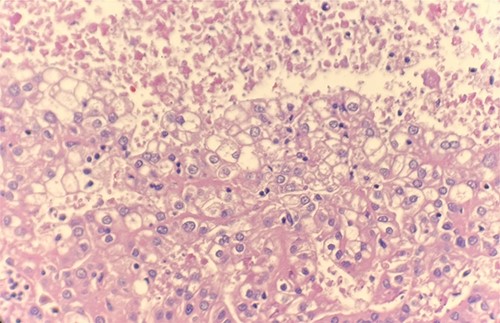

Microscopic examination revealed that clear cell RCC (Fig. 1), papillary RCC type 1 (Fig. 2), and papillary RCC type 2 (Fig. 3) were present in the right kidney, and papillary RCC type 2 was present in both kidneys. Immunostaining showed that tumor cells were positive for alpha-methyacyl-CoA racemase (Fig. 4), CD10, CK7, and vimentin, and negative for CD117.

Microscopic examination reveals compact tumor nests and sheets of cells with clear cytoplasm and distinct membrane. HE stain 40x.